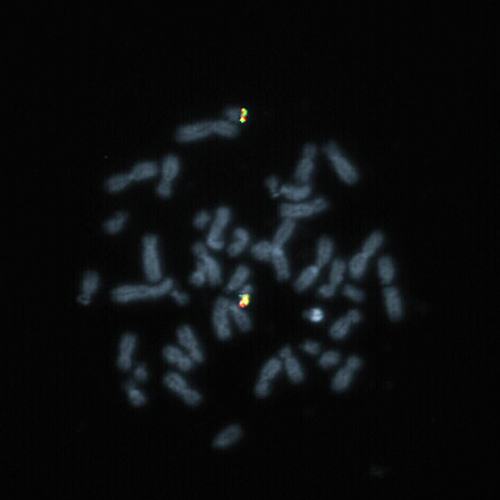

BCL2 (18q21) Break probe hybridized to a normal metaphase.

Follicular lymphoma is a mature B-cell lymphoma characterized by the presence of the t(14;18) translocation that juxtaposes the BCL2 locus on chromosome 18q21 to the immunoglobulin H (IGH) locus on chromosome 14q32, resulting in the overexpression of the anti-apoptotic protein BCL2. Next to IGH, other translocation partners to BCL2 are also known (e.g. IGK at 2p11.2 and IGL at 22q11). A break or split assay is therefore best suited to detect rearrangements of the BCL2 gene region at 18q21. The BCL2 (18q21) Break FISH probe is optimized to detect translocations involving the BCL2 gene region at 18q21 in a dual-color, split assay on metaphase/interphase spreads, blood smears and bone marrow cells.